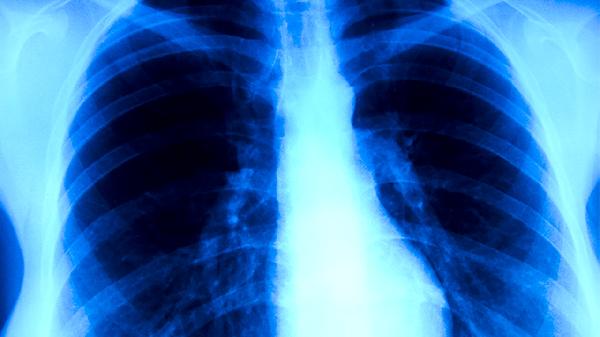

肺炎支原体lgm抗体阳性吃什么药

肺炎支原体IgM抗体阳性患者可遵医嘱使用阿奇霉素片、盐酸多西环素片、左氧氟沙星片、罗红霉素胶囊、克拉霉素片等药物。肺炎支原体感染通常表现为咳嗽、发热、咽痛等症状,需结合临床症状与实验室检查综合判断。